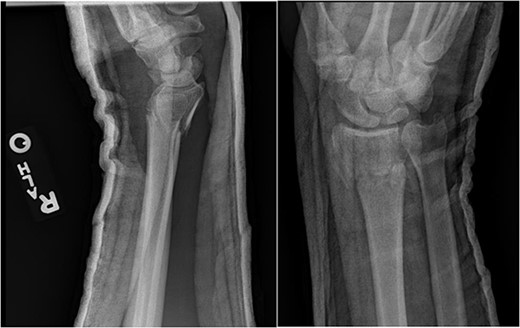

At 3-month postoperative follow-up, grip strength was 18 lbs on the right and 25 lbs on the left. Pinch strength was 9 lbs on the left and 7 lbs on the right. At 5-month follow-up, the patient was transporting himself using a wheelchair, and his wrist pain was well controlled. At 7-month follow-up, grip strength was improved to 30 lbs on the right and 45 lbs on the left; pinch strength was 3 lbs on the right and 8 lbs on the left. Right wrist motion demonstrated 40° of flexion, 20° of extension, and full unlimited pronosupination. Radiographs demonstrated a healed distal radius fracture with no signs of arthrosis at the new radiocarpal joint (Fig. 4). At 1-year follow-up, the patient continued to progress functionally with no new complaints of pain. At 2-year follow up, the patient’s Disabilities of the Arm, Shoulder, and Hand score was 35.83.

AP and lateral views at 7-month follow-up demonstrating a healed right distal radius fracture without arthrosis at the new radiocarpal joint.